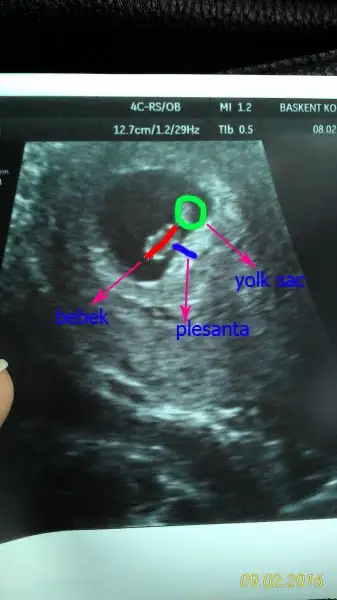

plesanta solda karındansa ultrason erkek bunda da tutmuş cnm... kesenın patlıcanımsı görüntüsü yana çevrildiğinde solda kalıyor...

Evet karından usg, bu fotolara hangi açıdan bakıyorsun, ne tarafa çeviriyoruz patlıcan gibi olunca:) ve plasenta yolk sac nerede işaretleme imkanın var mı, ben de anlamak istiyorum gerçekten:)

sivri taraf yukarı gelecek sekilde çeviriyorum. photoshop ile işaretleyeyim

sinemnur sinemnur cnm seninkini işaretledim ancak bir önceki haftayı da görsem tam olacaktı.